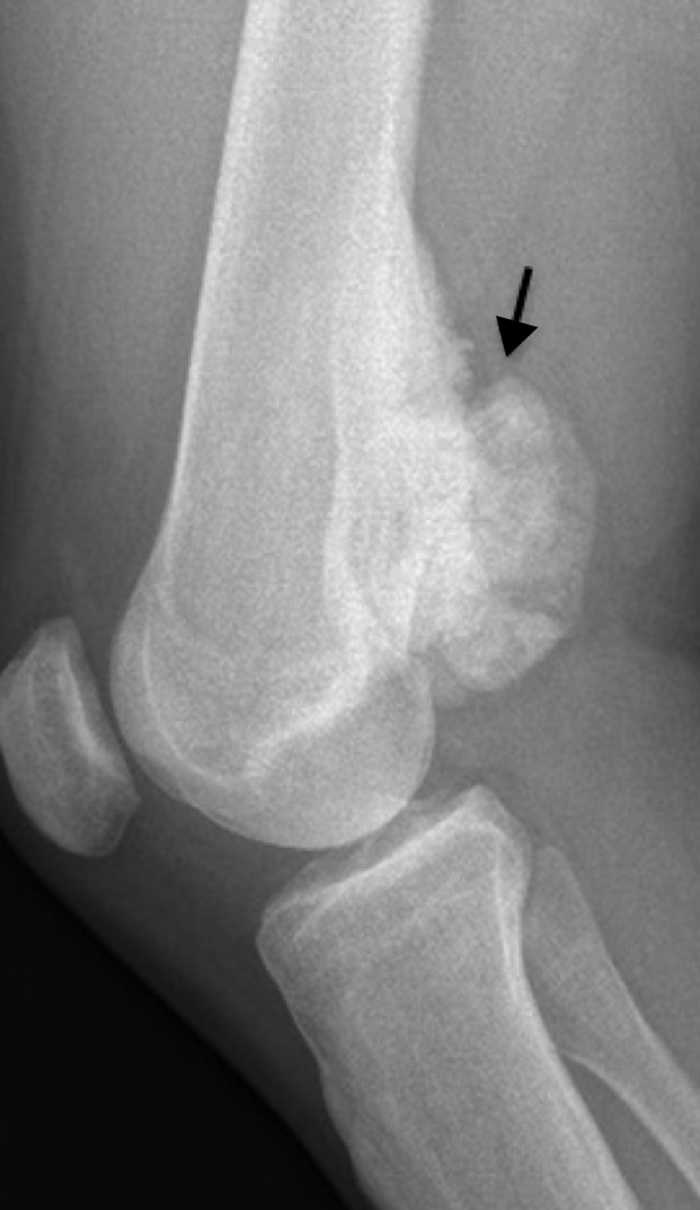

El segundo caso fue otro varón de 23 años con una tumoración dolorosa en el hueco poplíteo, que había crecido en el último mes. El paciente no tenía antecedente traumático ni fiebre o síndrome constitucional. A la palpación la tumoración era firme y no móvil. La radiografía simple mostró una lesión de localización metafisodiafisaria, dependiente de la cortical femoral y de dudosa continuidad con la medular, con morfología irregular y matriz osteoide (fig. 3). En la TC se confirmaron los hallazgos (fig. 4a) y, además, se detectó un área de posible afectación de la medular periférica (fig. 4b). Se completó el estudio con RM y gammagrafía ósea (no mostradas) y, ante la sospecha de malignidad, se realizó una biopsia con resultado de POPB.